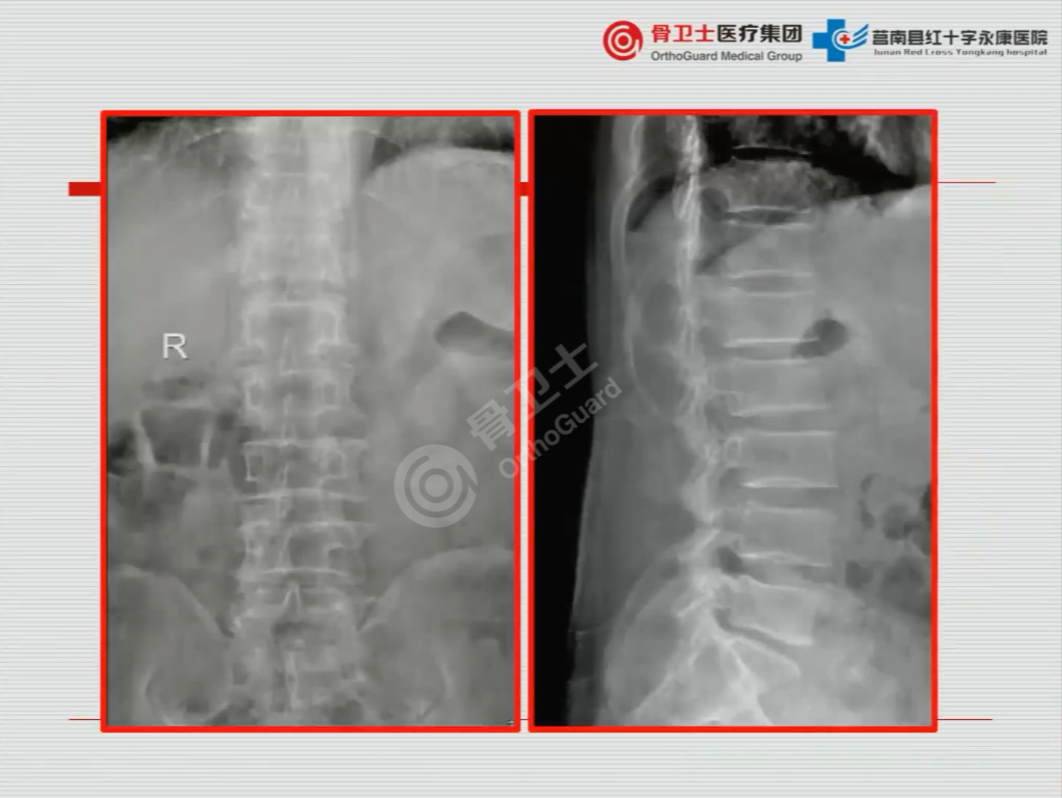

既往史:患者既往6年前因腰5椎体2度滑脱于其他医院行椎管减压椎间融合内固定治疗。

诊断:通过对患者查体及综合影像资料,医生认为,患者行走无力、右下肢不自主抽动,双上肢无异常,考虑为胸段脊髓原因引起,行胸椎MRI及CT检查后,诊断为胸椎管狭窄并黄韧带骨化;腰椎术后。

▲患者影像资料

吴闻文教授认为,该患者从胸8到腰1节段都有狭窄,选择对下半部分减压,效果不错。该患者胸腰段有后凸畸形,脊髓是有张力的,椎管还是有狭窄。张力往往跟运动有关,如果条件允许,可以选择胸8固定到腰2,不一定做截骨,整个减压以后,用棒子的力量,像矫形一样,把后凸减少一些,这样,不用截骨也会少量减少后凸,对脊髓张力、缺血、恢复非常有利。